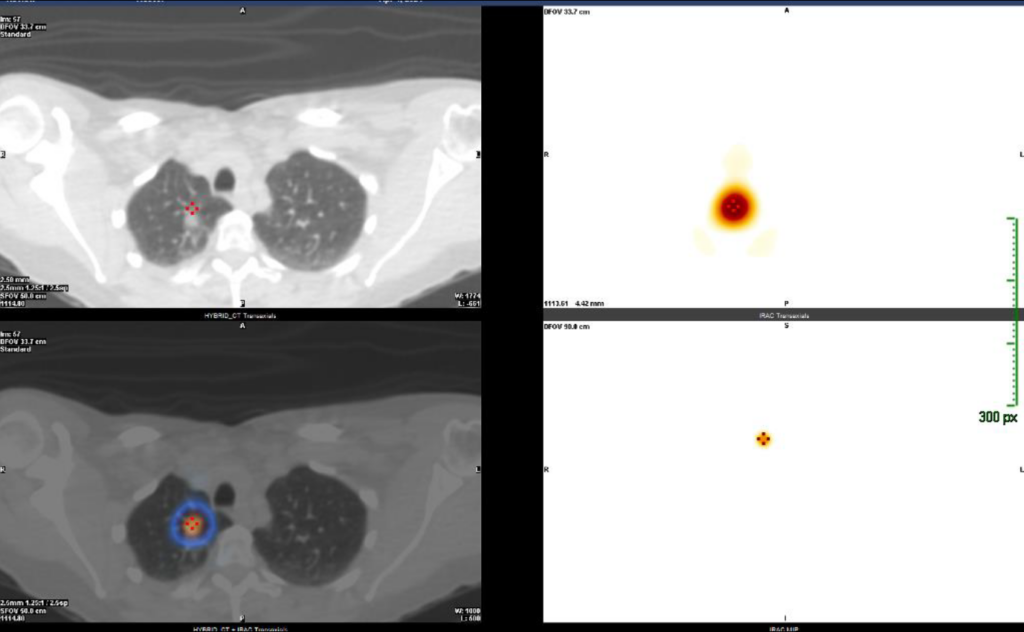

CASO 1: Mujer de 51 años. Nódulo subsólido de 10 mm en LSD detectado como hallazgo casual TC cervical, de lento crecimiento desde 2021.

Imagen TC (arriba izq.), SPECT/TC (abajo izq.) y SPECT (derecha).